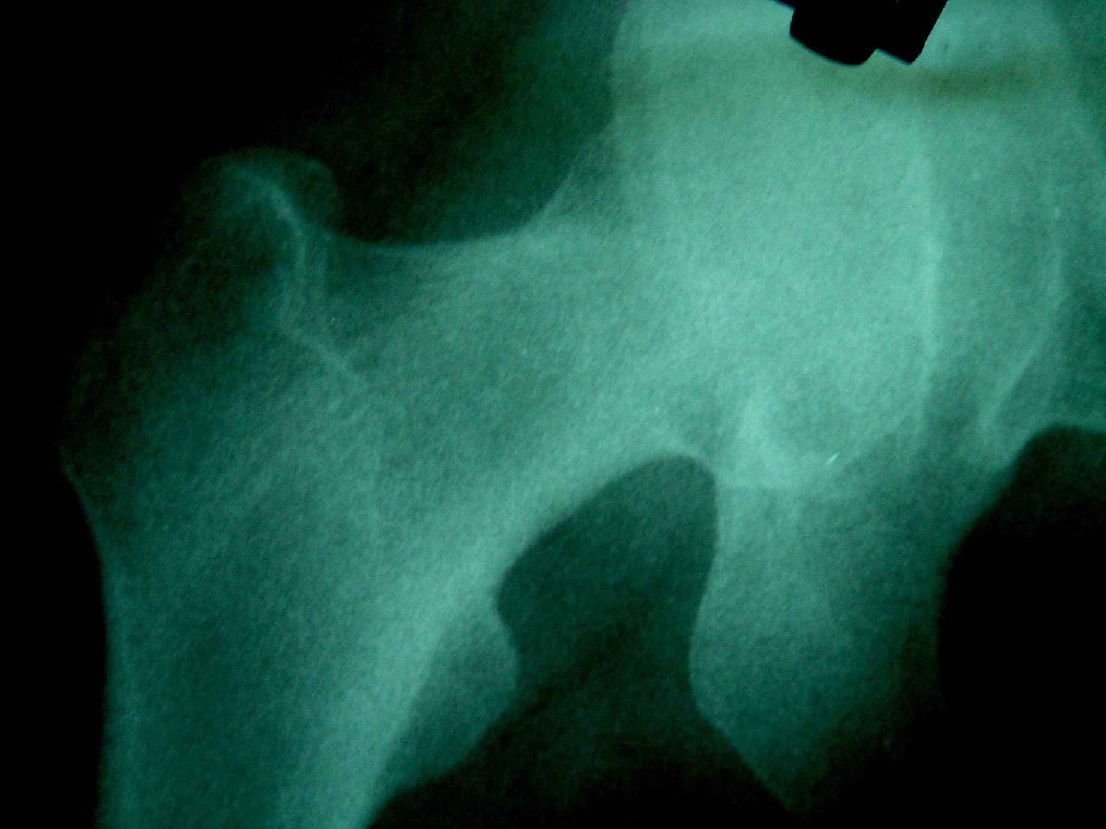

患者,女,因外伤就诊。摄骨盆及右股骨。当时报告骨盆未见明显异常,右股骨中段粉碎性骨折。五天后行股骨中段骨折内固定手术,术中摄床边片示股骨颈骨折。现把术前和术中图像上传。请大家高诊,分析股骨颈骨折是术前漏诊还是其他原因。术前骨盆片右股骨颈显示欠佳是由于股骨中段骨折无法将股骨颈完全显示。

这里还有几张该患者的几张x 光片。

现在我向大家请教,股骨中段粉碎性骨折的同时股骨颈也会骨折吗,另外如图所示该患者股骨颈骨折线是我们常见的由外伤引起的骨折线吗。

术前由于位置原因使股骨颈未全部显示,骨折线与股骨头重叠,骨折也可以使股骨颈缩短

回头看术前片,可见一低密透光区.

楼主给我们大家提供了非常好的片子,感谢!该片股骨颈的骨折术前看不到骨折。这个和体位也有关,但是我们都知道,那些标准的体位是给健康人设计的,外伤比较重的往往都无法标准投照。不知道同行们有没有这样一种感受:发现明显的问题了,就心里比较踏实了,舒坦了,就不容易对其它细节仔细观察了。如果没有发现明显的问题,就仔细的翻来覆去的看。所以这个片子给我们很大的教训:仔细阅片!即便是已经发现问题了。如果非要给鸡蛋里面挑骨头,我认为楼主忽略了右髋关节囊的肿胀,诊断报告应该提一下。外伤的病人我最怕股骨颈的漏诊,一般我都要看软组织。我是一个小医院的,我深有感触,发现骨折不是功劳,而漏诊却是事故,还遭受别人耻笑:放射科的连骨头断没断都看不出来!

关于楼主说的骨折线的形态,的确和一般外伤的有种不太一样的感觉,上方裂隙较明显,下方骨皮质“连续”,我认为成年人应该是全部断了的,不全骨折的可能性非常非常小,该片恰好无法全部显示骨折线。骨折线的形态不能判定术前还是术后骨折。以上只是个人小小看法,请各位老师指正为谢!